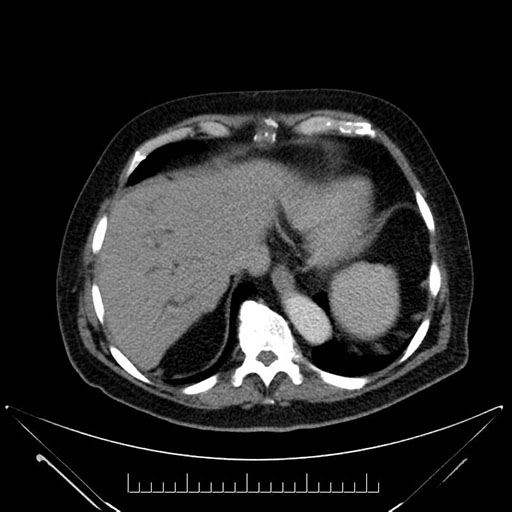

Axial - stented